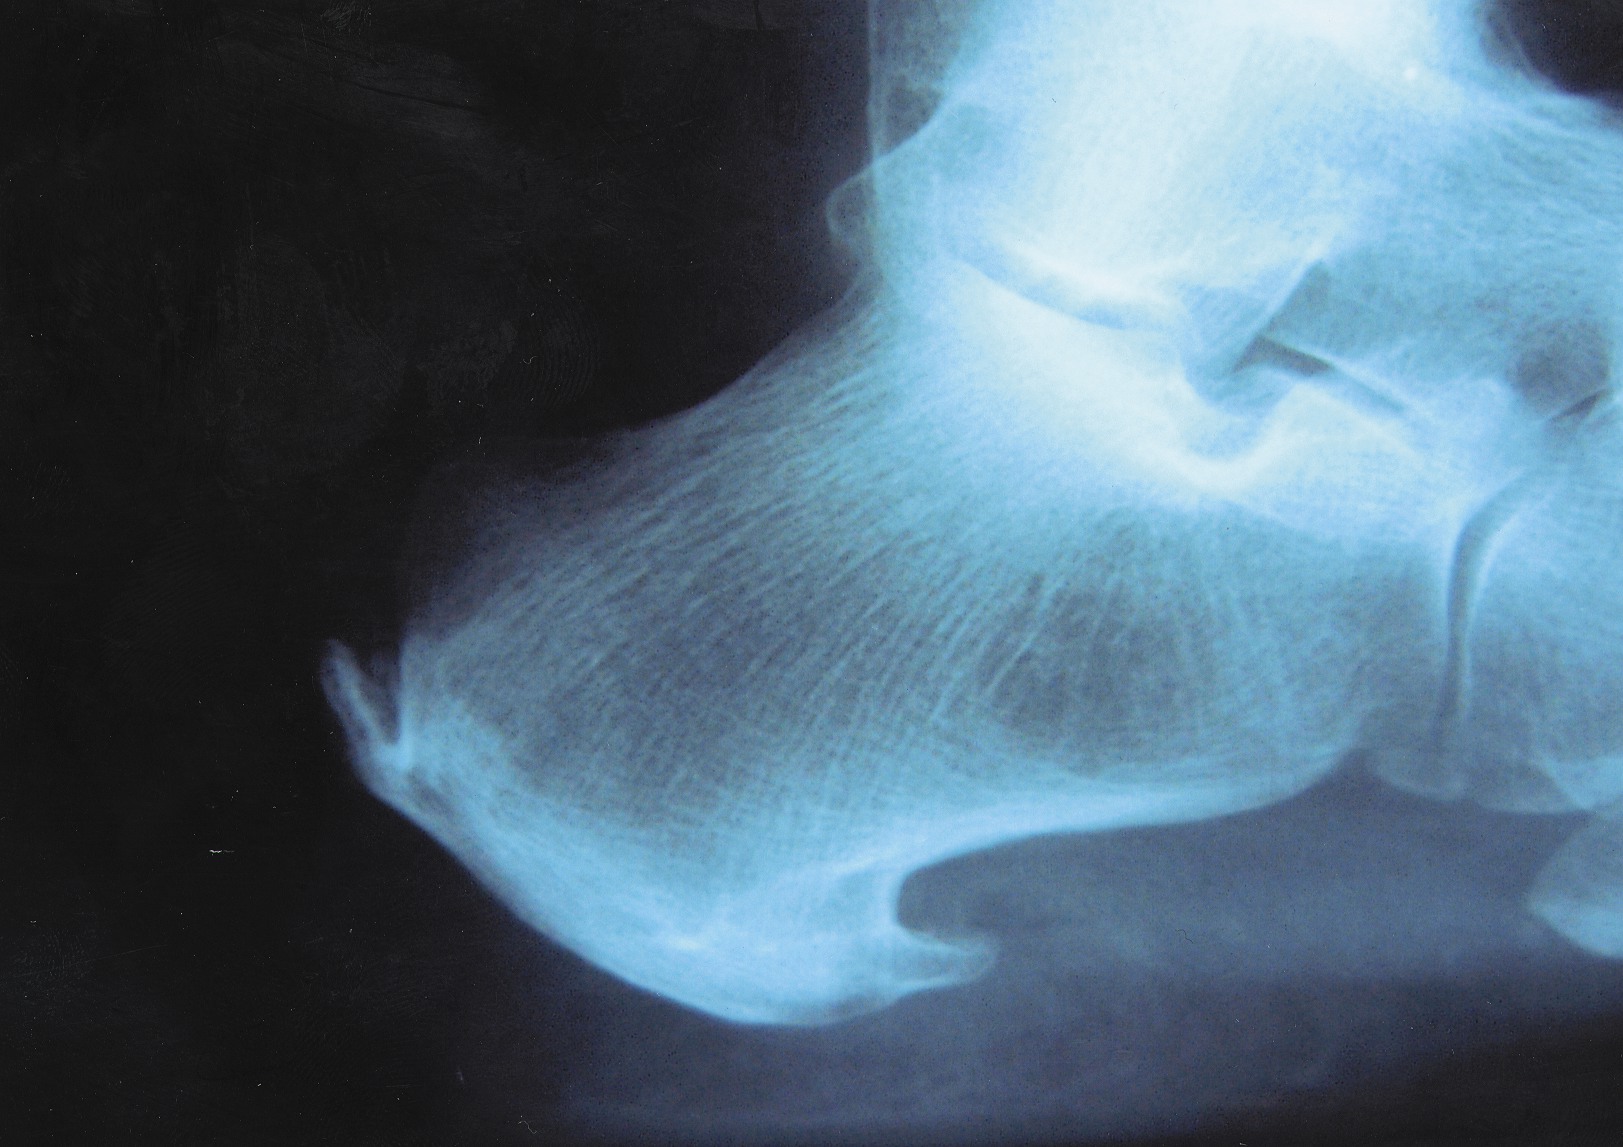

Tendinosis is one of those diagnostic terms that took me a while to truly understand. People most often use this term in relation to the Achilles complex but tendinosis can be related to any tendon of the foot or ankle. In most cases, tendinosis is associated with the tendons about the ankle and the most commonly affected tendons are the Achilles, posterior tibial and peroneals. While tendinosis is a very simple concept to explain, it is a far more difficult concept to truly understand and treat. Essentially, tendinosis involves the fraying or scarring of the fibers of the associated tendon and the replacement of a small or extended region of the tendon with scar tissue or fibrous tissue. The level of scar may be palpable to pressure on the associated region or may be microscopic in nature. There may be a bulbous region of damage or very small, scattered regions of damage. When tendinosis involves the posterior tibial or peroneal tendons, there is no associated peritenon and accordingly no peritenonitis or peritenosis. The most common regions of tendinosis are at stretch areas such as the associated malleolar bends, the navicular insertion for the posterior tibial tendon and the fifth metatarsal base for the peroneus brevis tendon. There are also far less visible signs of problems and one may define the major pathology with an ultrasound or an MRI of the region. The Achilles is a totally different animal and may have many different pathology findings due to the fact that there is a tendon, a prominent insertion site and a paratenon.

The overall result with the Achilles tendon pathology is that one can have a peritenonitis, a peritenosis, a tendonitis, a tendinosis, a partial tear, an exostosis or any combination. For the sake of this article, we will only address the tendinosis concept and leave the treatment of Achilles tendon pathology for a subsequent article. That said, we now understand that tendinosis is a fibrotic replacement of the true substance of a tendon with possible microscopic or small partial tears. When it comes to mild internal pathology, we know it is best to visualize this with an MRI or ultrasound. How does this pathology occur? The truth is it is not well understood in detail. The general concept is there is tension along the line of pull of the tendon, resulting in microscopic or macroscopic trauma to the tendon and a resulting partial tear of the tendon. The tearing may also be microscopic or macroscopic in nature. As there is minimal pain and discomfort on a daily basis at first, patients will continue to perform their regular activity and continue the microscopic damage to the region. Over time, the accumulation of trauma causes a replacement of the fibrils of tendon with scar tissue. The result is a tendon that is less flexible and stiffer with possible internal bulbous or linear tears, and degeneration of the tendon. One can best note this in a large tendon such as the Achilles. On a microscopic level, clinicians may see small linear tears and scar formation, mild thickening of the tendon and mild internal cystic changes. Over time, the scarring and cystic changes increase, and there may be thickening and bulbous enlargement of the tendon, which one can easily see through the skin and palpate with pressure along the tendon. With further neglect, there may be frank tears of the tendon or even complete replacement of a section of tendon with either bone or complete scar formation. Dealing with the underlying problem is a multifactorial situation. What is the patient’s overall goal (competitive sports, walking, no pain)? What is the patient’s lifestyle (sedentary, very active)? How bad is the pathology of the tendon (complete scarring, a severe tear, microscopic damage)? How long has the problem existed (many years, one month, a couple of days)? What is the overall makeup of the foot function (equinus, cavus, valgus, forefoot pathology and malalignment)? Once you have assembled the entire picture in regard to diagnosis and treatment goals, you can proceed with a course of treatment.